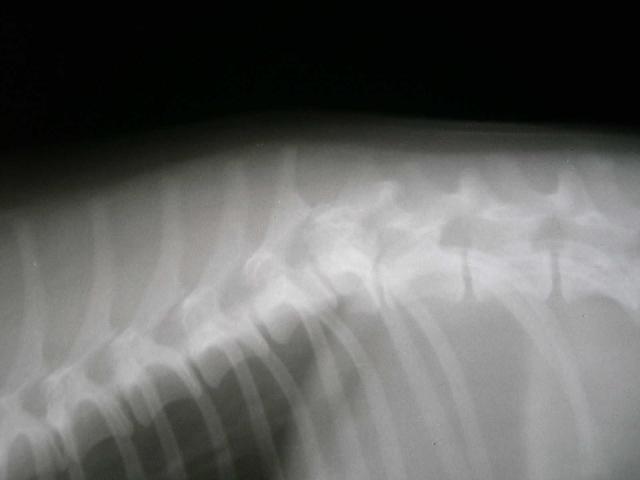

Fractured Spine of Dog

This dog was hit by a car and fractured his spine. Luckily, he has made a recovery and is able to walk thanks to the attentive and devoted care of his owners.